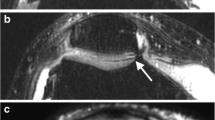

a Transverse FS IW MR image obtained on a 3T MRI unit showing truncation artifact (arrow in a) that gives a “false” laminar appearance to the patellar cartilage. Truncation artifacts typically appear as fine parallel lines immediately adjacent to high-contrast interfaces. Sagittal FS IW images in b flexion and c extension in a 36-year-old asymptomatic volunteer showing a variable signal intensity of the anterior (black arrows in b and c) and posterior (white arrows in b and c) cruciate ligaments related to the magic angle effect. Sagittal FS IW images in d flexion and e extension, and f sagittal PD fat-suppressed images in extension in the same volunteer obtained on a 3T MRI unit: the signal intensity of the cartilage (arrows) and the chondro-osseous junction (arrowheads) varies according to the orientation within the main magnetic field due to the magic angle effect. The signal intensity of cartilage (small arrows in e and f) also vary according to the TE. Note the fine meniscal high signal intensity line (f) that does not univocally reach the surface, seen on one image, and not visible on IW FS images (e), interpreted as no tear